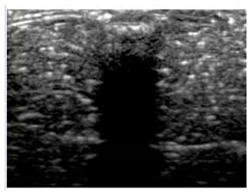

3.3. B-Mode Images

3.5. Echogenicity

4.1. Ultrasonography and Aerogel Dimensional Analyis

| Aerogel Type | US Image | Normalized Intensity Map | 3D Intensity Map | |

| 1 | Muscle |  |  |  |

| 2 | X-silica |  |  |  |

| 3 | X-silica-La2O2S:Eu |  |  |  |

| 4 | SMPU-Mix-14 |  |  |  |

| 5 | SMPU-Mix-18 |  |  |  |

| 6 | BRF-CA |  |  |  |

| 7 | ARF-CA |  |  |  |

| 8 | X-Ca-Alg-2 |  |  |  |

| 9 | X-Ca-Alg-1 |  |  |  |

| Aerogel Type | Imaging Frequency (MHz) | Optimal Frequency (MHz) | Echogenicity | Image Characteristics | Impedance Mismatch (%) | |

| X-silica | 6.5–13.4 | 13.4 MHz | Hypoechoic | Least Hyperechoic | Distinct linear boundary | 92.03 |

| X-silica-La2O2S:Eu | 6.5–13.4 | 13.4 MHz | Hypoechoic | Least Hyperechoic | Distinct linear boundary | 90.28 |

| SMPU-Mix-14 | 6.5–13.4 | 11 MHz | Hyperechoic | Moderately Hyperechoic | Irregular boundary | 98.33 |

| SMPU-Mix-18 | 6.5–13.4 | 11 MHz | Hyperechoic | Moderately Hyperechoic | Irregular boundary | 98.23 |

| BRF-CA | 6.5–13.4 | 13.4 MHz | Hyperechoic | Hyperechoic | Waterfall appearance | 97.16 |

| ARF-CA | 6.5–13.4 | 13.4 MHz | Hyperechoic | Hyperechoic | Waterfall appearance | 97.12 |

| X-Ca-Alg-2 | 6.5–13.4 | 11 MHz | Isoechoic | Strongly Hyperechoic | Irregular boundary | 98.03 |

| X-Ca-Alg-1 | 6.5–13.4 | 11 MHz | Isoechoic | Strongly Hyperechoic | Irregular boundary | 97.97 |